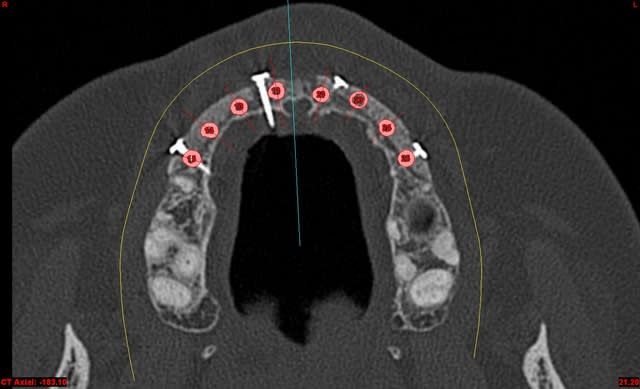

dentiste57 écrivait:

--------------------

> et là ?

> greffe selon ta méthode ?

Cross section dhvkc8 - Eugenol

3d dt3qom - Eugenol

Overview uqcp6u - Eugenol

expansion, c'est plus cool!